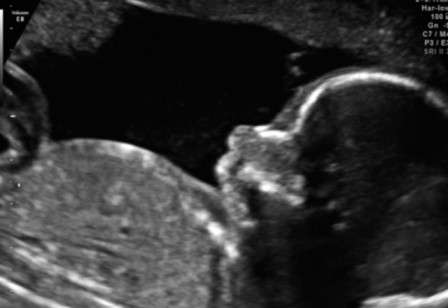

najpierw cesarke sama wymusilam, ale po ostatnim usg, gdy okazalo sie sie, ze chlopiec jest duzo wiekszy od dziewczynki, a jest jako twin 2, to ze wskazania mam cesarke, zeby nie bylo komplikacji